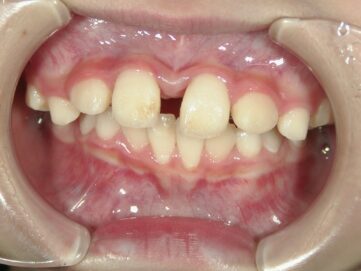

最近では歯並び・噛み合わせが悪い子供が増えてきています。成長期における生活環境や食生活による顎の成長不全が原因だと言われています。噛み合わせが悪いと歯がしっかりと生えることができなかったり、八重歯や出っ歯などの 不正咬合となってしまう可能性があります。

子どもの頃の早い時期から矯正治療を行うことで、顎の発達を利用しながら、歯を動かしていくことが可能です。

子どもの頃は骨が柔らかいので、歯が動きやすく治療がスムーズに進行します。また、痛みも軽いことが多いです。

しかし、子どもの頃の矯正治療に関しては骨が柔らかく、顎の発達も利用できるため歯が動かしやすく、歯を抜かずに治療できる確率が高いのです。

第1期治療(3~10歳)から小児矯正を治療開始できれば、第2期治療(中学~成人)から矯正治療を開始する場合と比較してみても、治療期間を短縮できるという考え方もあります。永久歯が生え揃うスペースを確保しながら顎の成長もコントロールしていくことができますので、大人になってからの矯正治療よりも短期間で終わることが多いです。もしくは、大人になってからの矯正治療が不要となる可能性もあります。